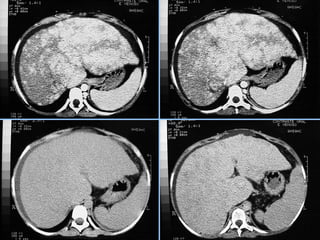

ESTEATOSE HEPÁTICA

ACENTUADA

• Ocorre uma diminuição na eficácia da TC de

identificar lesões focais hepáticas.

• Pode ocorrer uma inversão no padrão visual das

lesões focais, em relação às comparações usuais de

atenuação feitas com o fígado normal.

MULTINODULAR

• Forma mais rara de esteatose hepática.

• É fundamental a correlação com dados

clínicos e com estudos de RM para excluir

doença metastática.